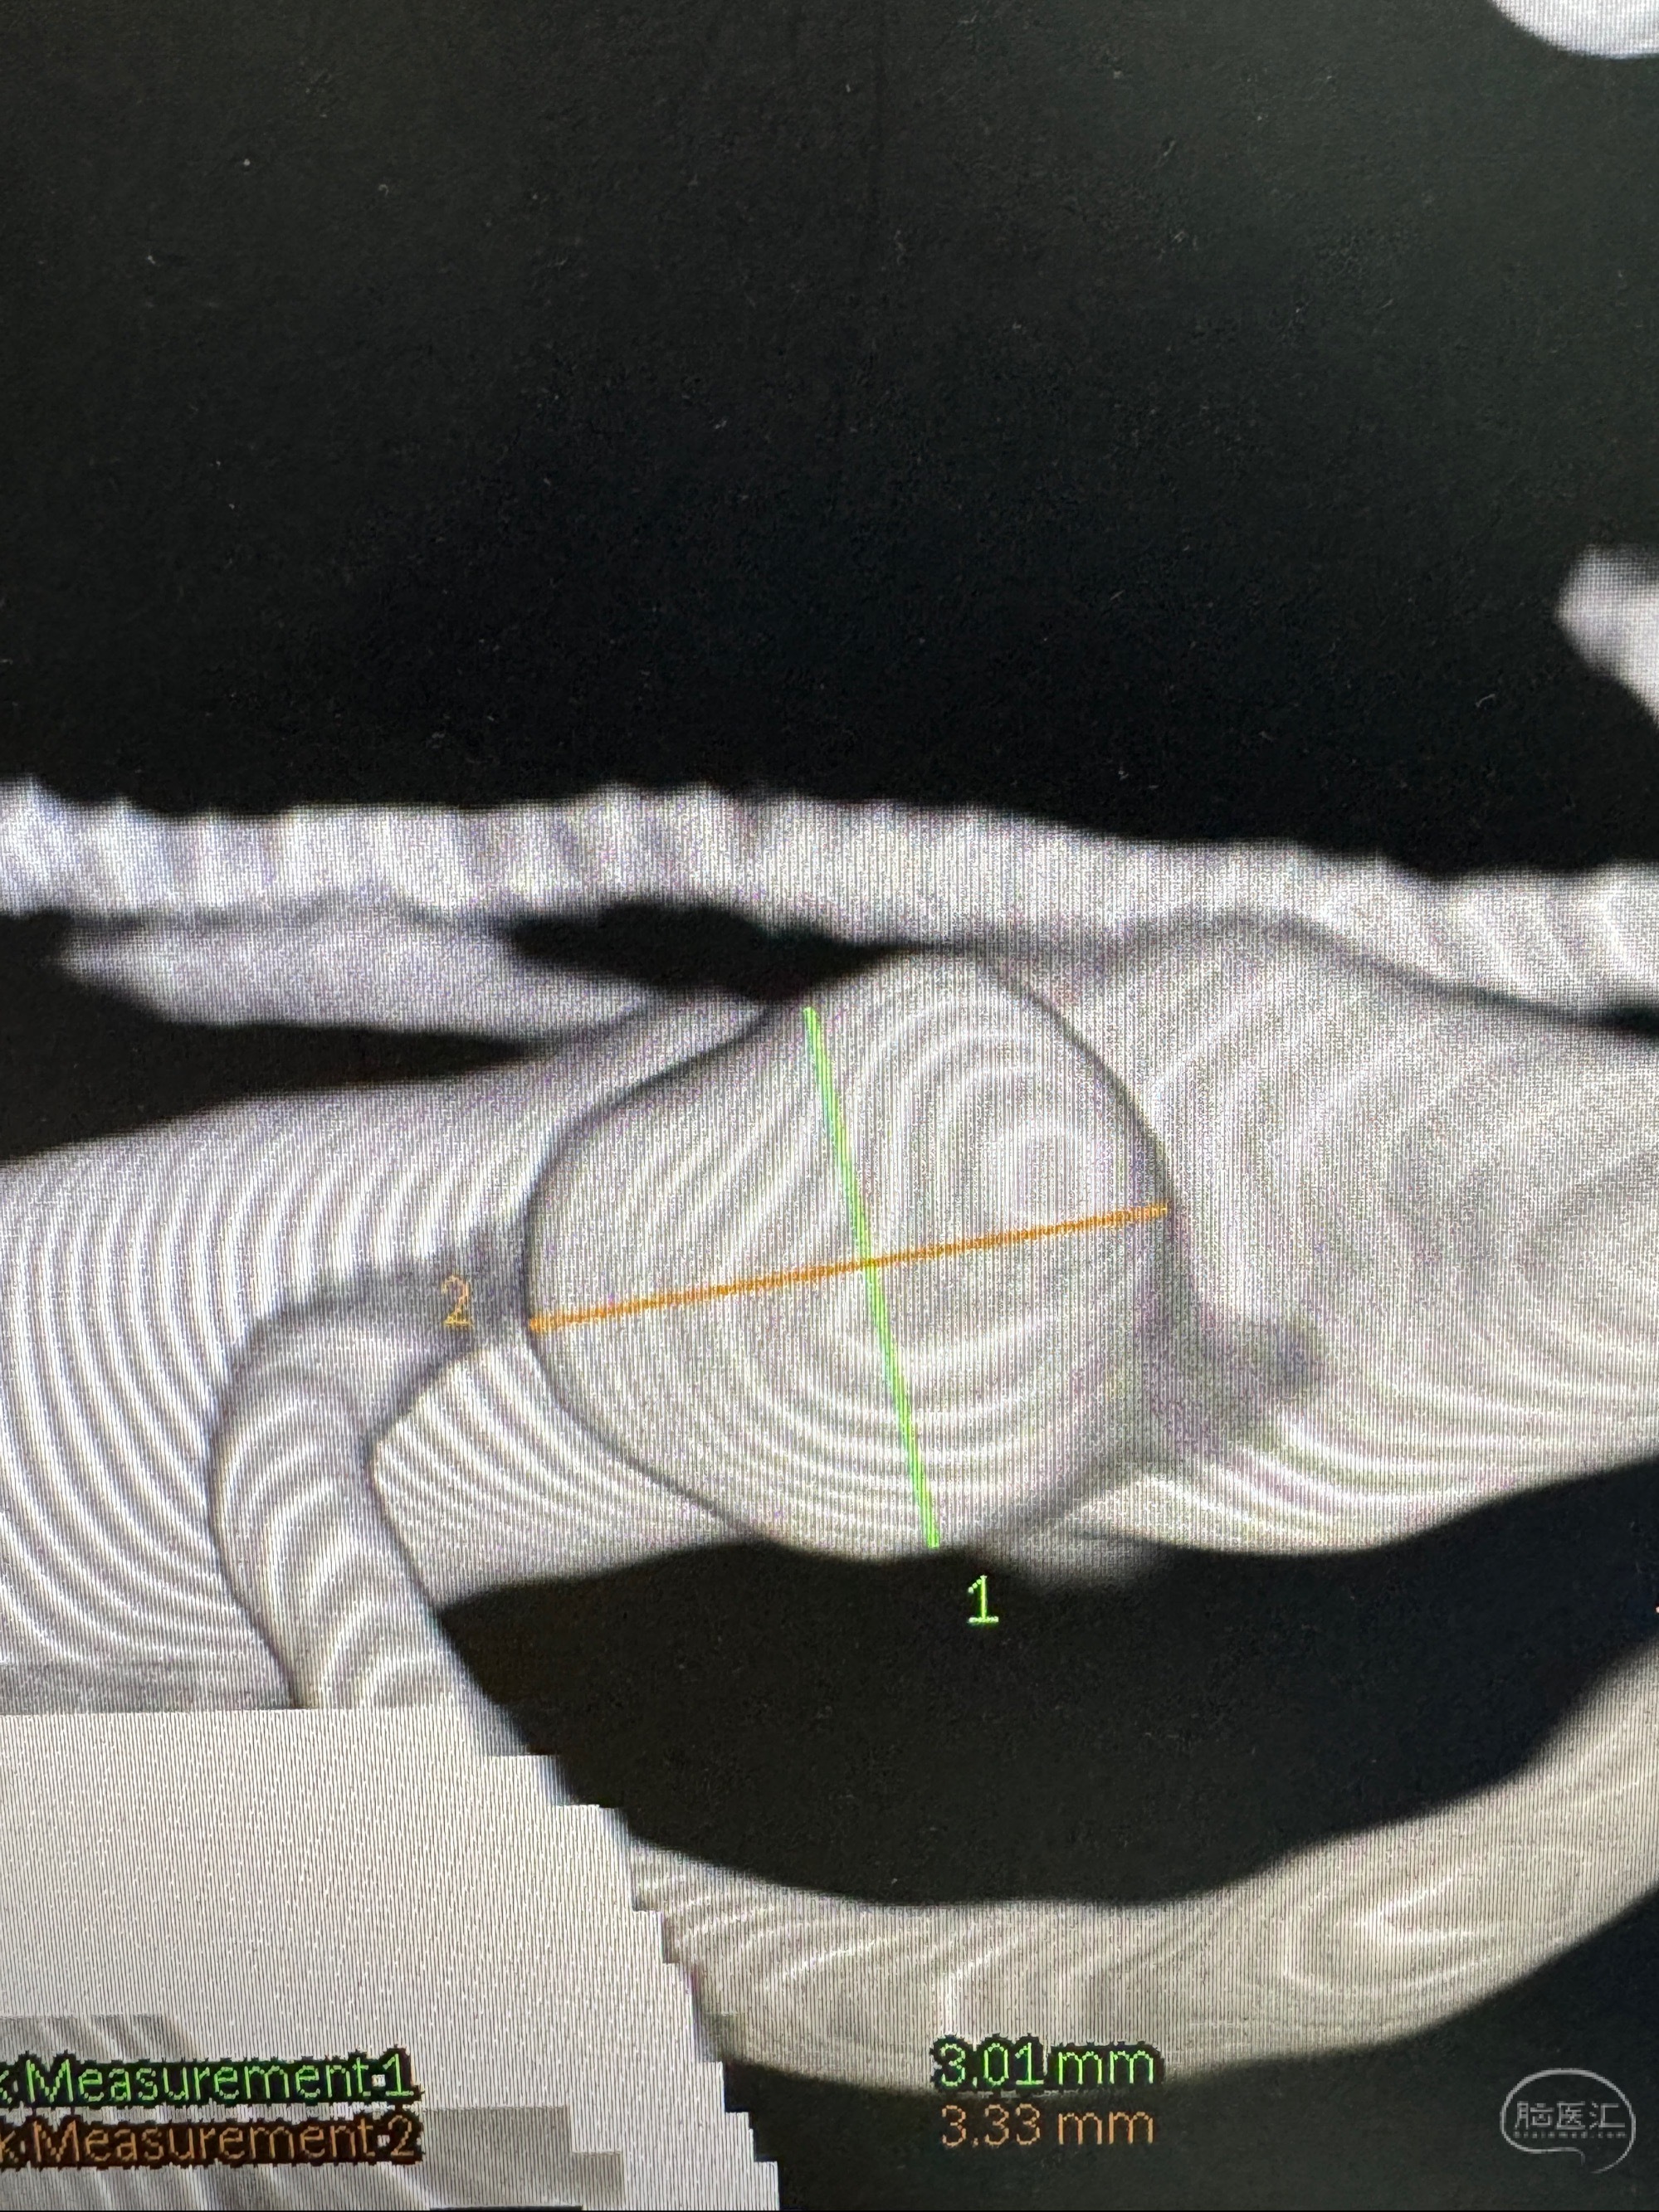

2023-06-26 安徽省立医院 头颅CTA:右侧大脑中动脉M1段动脉瘤,双侧颈内动脉虹吸段管壁钙化斑块,管腔无明显狭窄,双侧大脑中动脉M1段管腔狭窄;

2023-10-25 安徽省立医院 头颈部CTA:右侧大脑中动脉M1段动脉圆锥,主动脉弓混合斑块,双侧颈内动脉虹吸部钙化斑块,双侧大脑中动脉M1段硬化性狭窄,多灶性脑梗塞,老年脑改变;

2023-11-24DSA:右侧大脑中动脉下干起始部动脉瘤,约2.3*2.5mm,形态规则